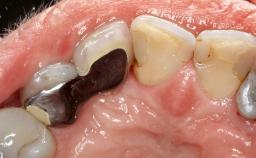

Surgical Management of Peri-Implantitis: Reconstructive Surgical Treatment with Three-Year Follow-up After Treatment

A 70-year-old female patient was referred by her general dentist to the periodontist for assessment and management of an infection associated with implant 36. The general dentist had noted suppuration on probing during examination.